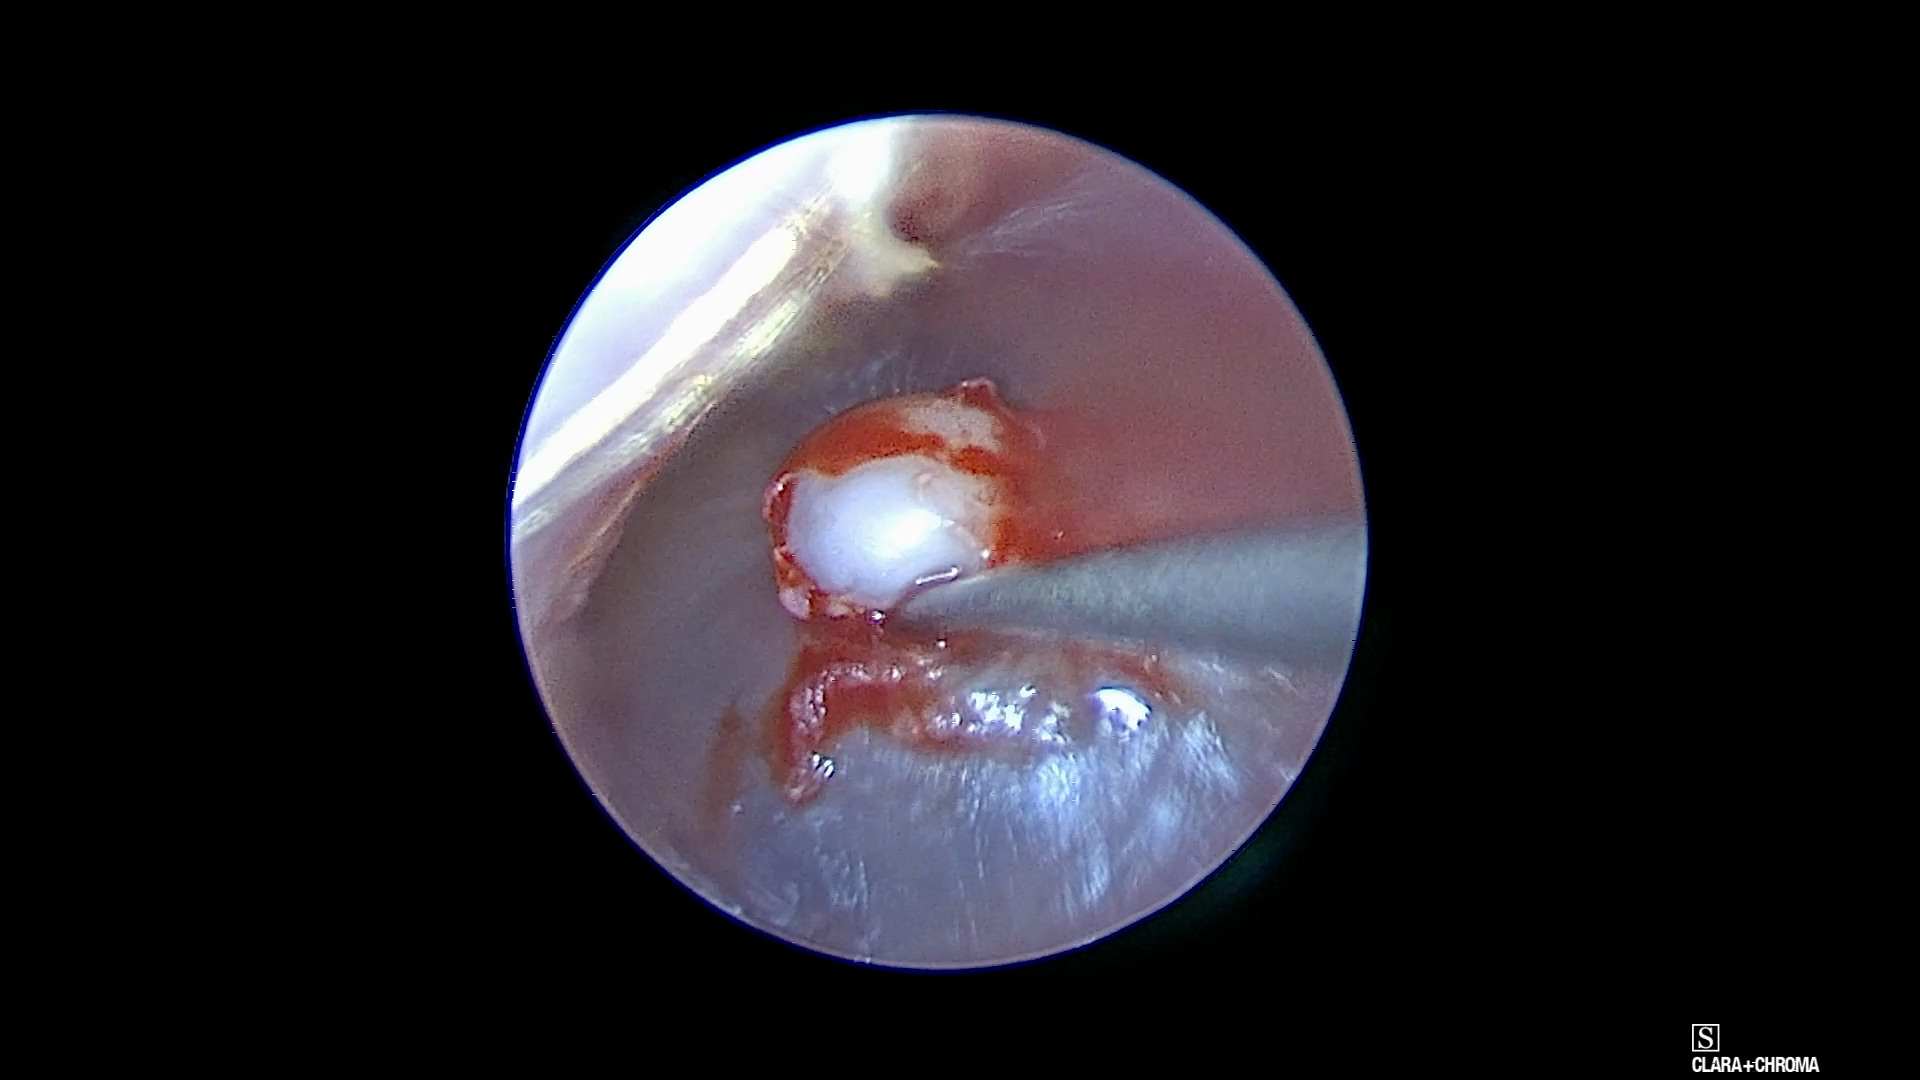

Watch the Full VideoA 3 yo girl was referred to the ENT clinic after her PCP noticed an abnormal TM on the left. She has a history of a 2 ear infections prior to presentation. She is asymptomatic, with no pain and no drainage from her TM. Her audiogram was normal. Her physical eventually revealed the presence of a relatively large keratin pearl on her TM, without obvious middle ear effusions. After a short period of observation the family decided to have it removed. The case was performed endoscopically in a trans-canal approach. The lesion was dissected mainly with a straight pick. The fibrous layer underneath was found to be intact and no myringoplasty was necessary. The patient was was seen again 2 months post-op and her TM was found to be normal with a normal audiogram.